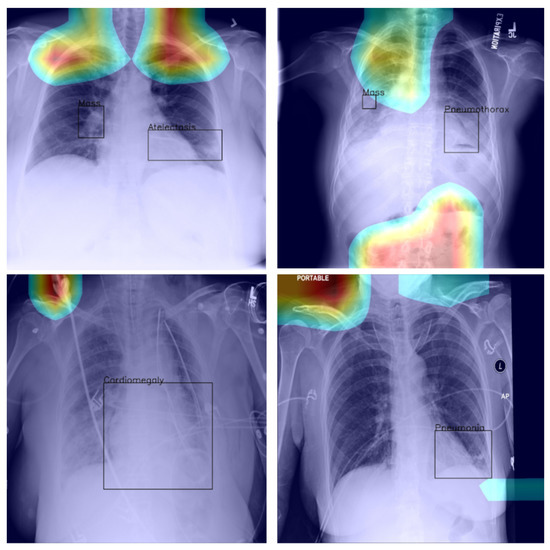

4.4. Saliency and Explainability

As we noted previously, using Grad-CAM, or indeed similar methods [27], it is possible to quantify and thus visualise the importance of different parts of an analysed image a network uses as the basis for its prediction. This can be helpful both in understanding why the model fails when it does as well in focusing an expert’s attention for further analysis and interpretation.

In the context of the ChestX-ray8 corpus, the labelling within it has been criticised by some [25]. This is hardly surprising, for the very manner in which the labels were extracted makes it impossible to consider them as the oracle ground truth. For instance, some pneumothorax images are of patients that have already had treatments indicated by a chest drains in the image. This can lead a network simply localising the drain and, based on this finding alone, label the image as belonging to the pneumothorax class, rather than as a result of the actual visual analysis of the presentation of the condition—see Figure 2, wherein the drain has been marked with an arrow.

Figure 4.

Example of a high-confidence correct label identification, despite the entirely incorrect disease localisation.

Last but not least, we found that when the heat map is significantly off course, this is often an indicator of there being confounding information—in the sense that it is not inherent information affected by imaging, but rather added by human experts such as radiologists and, as such, being assistive in correct labelling prediction, but misleading in the context of what the method is trying to achieve; see Figure 5—present in an image (e.g., various textual descriptors overlaid on the images). If unnoticed, such information can instil false confidence in the performance of a model. Thus, we were again drawn to make two conclusions and recommendations: it is important that confounds of this kind be explicitly stated, observed, and discussed in any research and that a thorough examination of the data and specific findings be made whenever an algorithm is evaluated.

Figure 5.

Examples of confounding information unwittingly aiding inference.